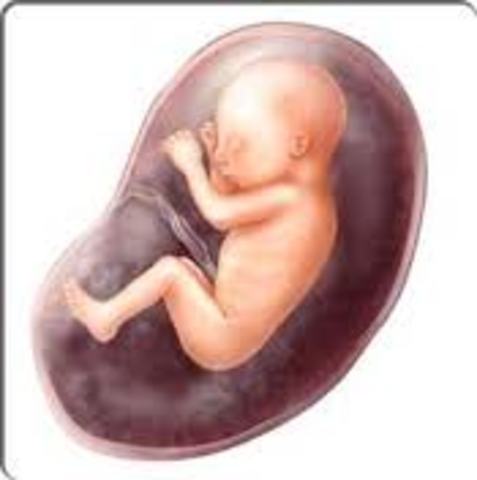

Fetal Development

Week 28

Your little work in progress is now about 2.5 pounds and almost 16 inches long. He's busy adding new skills such as blinking to an already impressive repertoire of tricks like coughing, sucking, hiccuping, and taking practice breaths. Your baby's sleep now includes the REM phase — and that means he could be dreaming already.

Week 32

Your belly’s increasing size is a definite clue that your baby is getting bigger every day, weighing in at over three pounds now. Also growing daily is his brain, which is actually starting to look like the real thing with those characteristic grooves and wrinkles. And now that your little genius can regulate his own body temperature and turn up the heat, he'll start shedding lanugo, the downy body hair.

Week 36

Your baby, who is now about six pounds and 20 inches long, with soft bones and cartilage to allow a safer journey through the exit door. Most of her systems are ready for prime time, though her digestion system — which has done only practice runs so far — will kick into gear as she takes her first suckle at the breast or bottle.